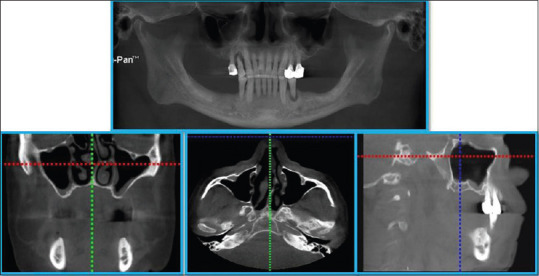

Abstract Image